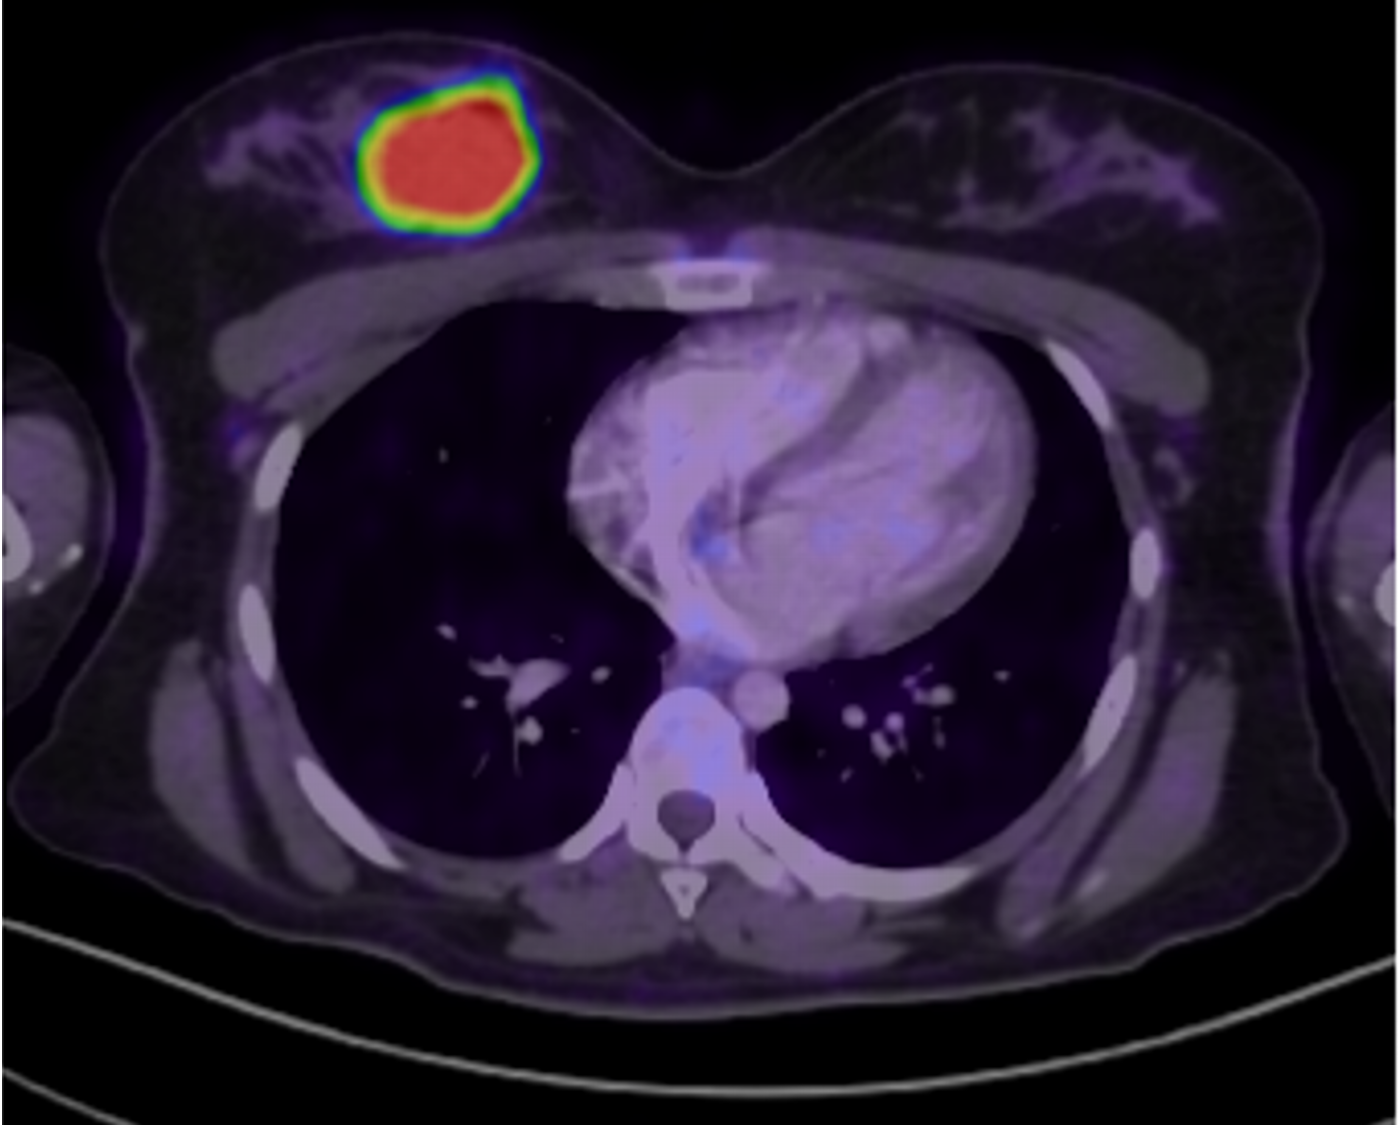

Imágenes de tomografía en adquisición axial en ventana para tejido blando, fase venosa, con su correspondiente correlación con imágenes de PET CT.

F. Mama derecha heterogénea, por la presencia de nódulo de composición sólida, homogénea, con realce periférico tras la administración de medio de contraste, localizado hacia cuadrantes internos y medidas aproximadas de 28×41 mm.

G. Imagen de PET CT a nivel de mama derecha identificando lesión sólida visualizada por tomografía, asociada a hipermetabolismo.